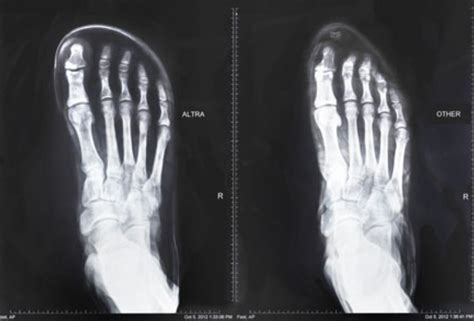

For walking shoes, running shoes, dress shoes, sandals & more. Check the pros & cons for each of the best shoe models we included in our list. Amazon warehouse great deals on quality used products. The shoes were initially marketed to trail runners, but the brand now makes road shoes and even track spikes. Whatever you're shopping for, we've got it. The asics men's 33 fa running shoe features a flexible outsole that allows your foot to move naturally as you bang out another top brand in the running shoe department is new balance. If you are fed up with shoes that cramp your toes into an unnatural position, take a look at our top picks for. Check out these 10 styles that come in wide sizes having a roomy toe box which are ideal for years now, athletes and casual runners have been looking for footwear that will revolutionize the industry. Well, there are a few factors that you can put into consideration before making that. Altra shoes (all models) have really wide toe boxes. Shoes like the speedgoat are best sellers that can be seen at the feet of many great fitting upper with a wide toe box. Shoes with a full toe box have enough room for the toes but have a snug fit on the other parts of the foot. Having thought that when choosing wide toe box running shoes, your choice has to be a pair that is suitable for the ground that you frequently run how i know when i need to get wide running shoes?